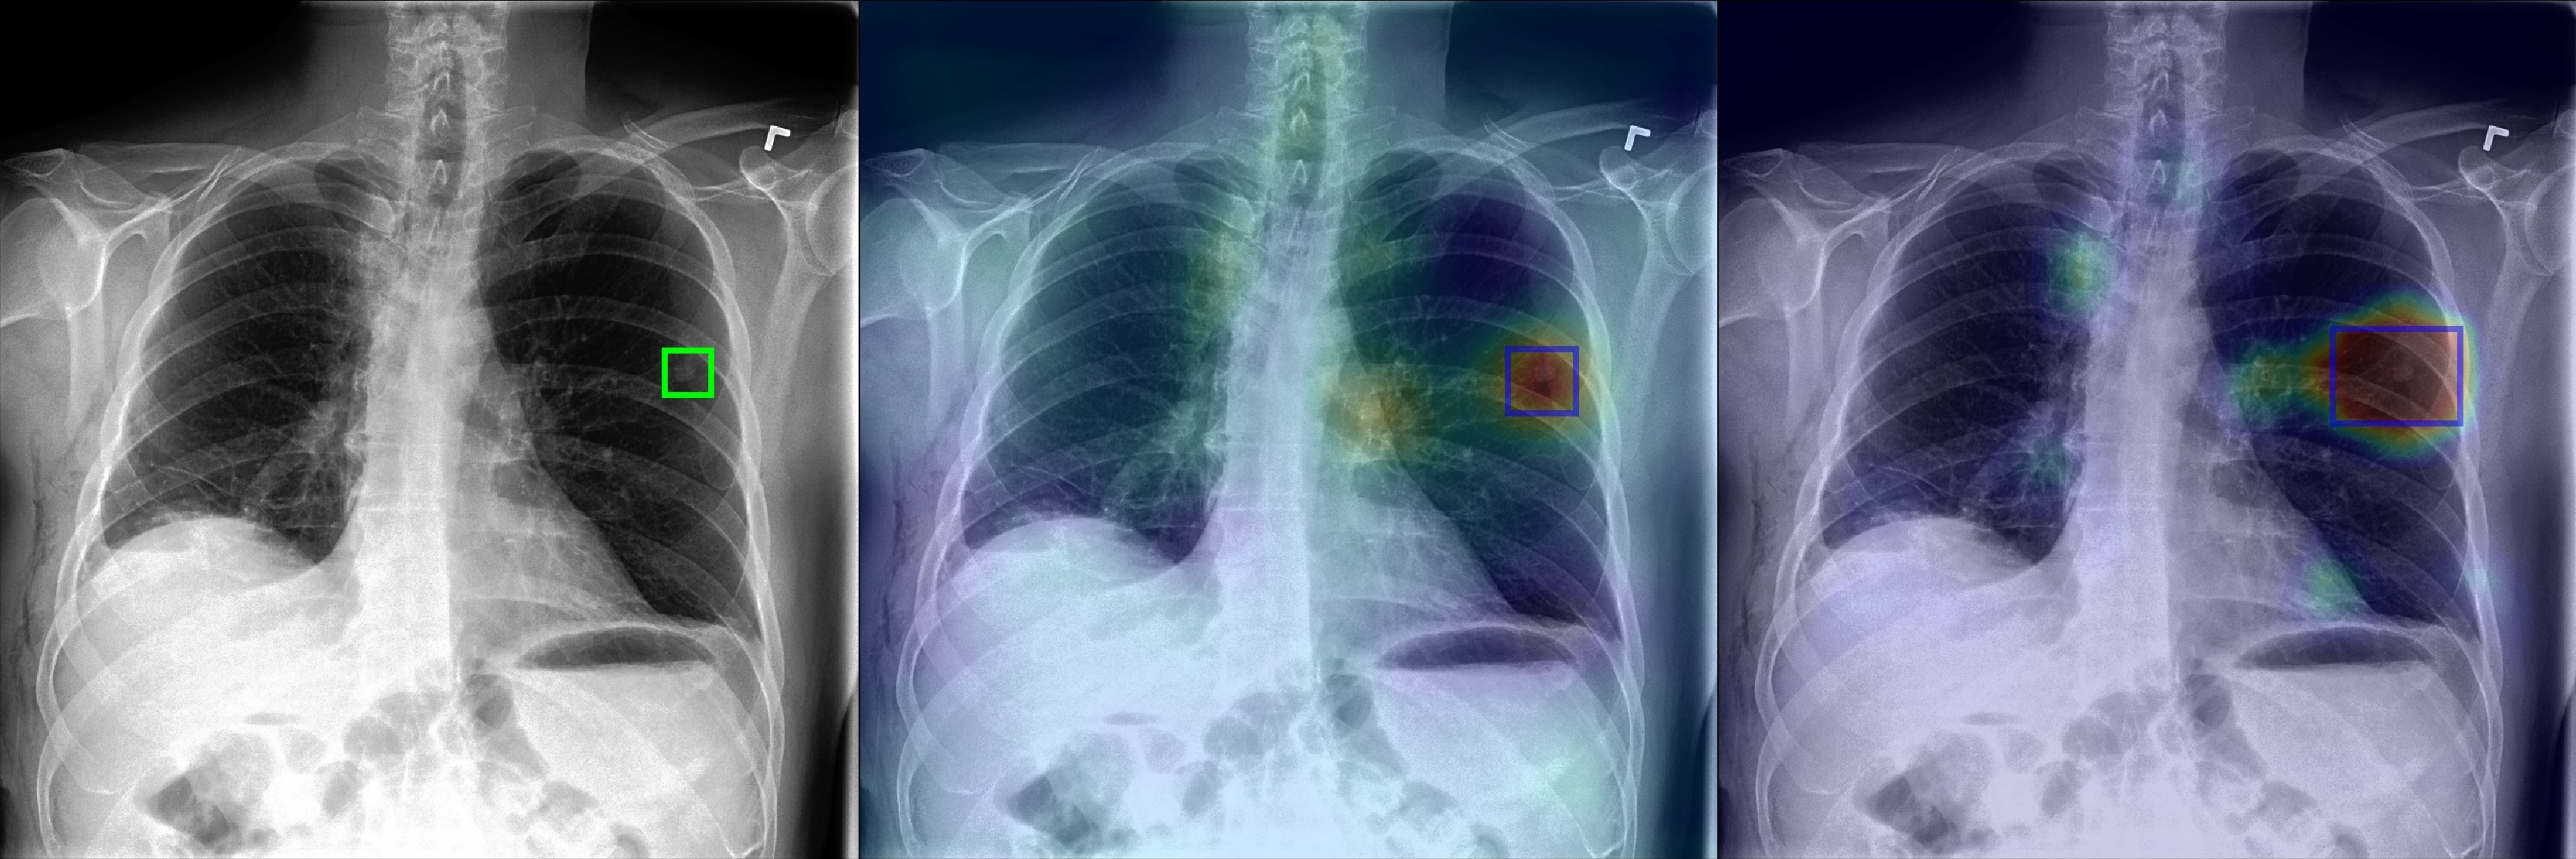

Figure 2 shows a few selected examples of the probability maps generated by PCAM pooling and the class activation maps generated by LSE pooling together with the predicted bounding boxes. Compared to the class activation maps, the probability maps are visually more clear with sharp boundaries around lesion regions. We attribute the improved visual quality to the probabilistic interpretation of the sigmoid-bounded class activation map and explicitly using it for training with global pooling.

We notice the probability maps generated by PCAM pooling tend to enlarge regions of interest in general than class activation maps from LSE pooling, especially when the ground truth regions are small, such as “Nodule” in Figure 2. This may explain the fact that PCAM pooling has relatively larger average false positives than CAM with LSE pooling.

(f) Nodule

Figure 2: Selected samples of localization heatmaps and their bounding boxes generated by LSE pooling and PCAM pooling on the test set of ChestX-ray14 [7]. In each subfigure, the left panel is the original chest X-ray with the ground truth bounding boxes (green), the middle panel is the class activation map and predicted bounding boxes (blue) by LSE pooling, the right panel is the probability map and predicted bounding boxes (blue) by PCAM pooling.